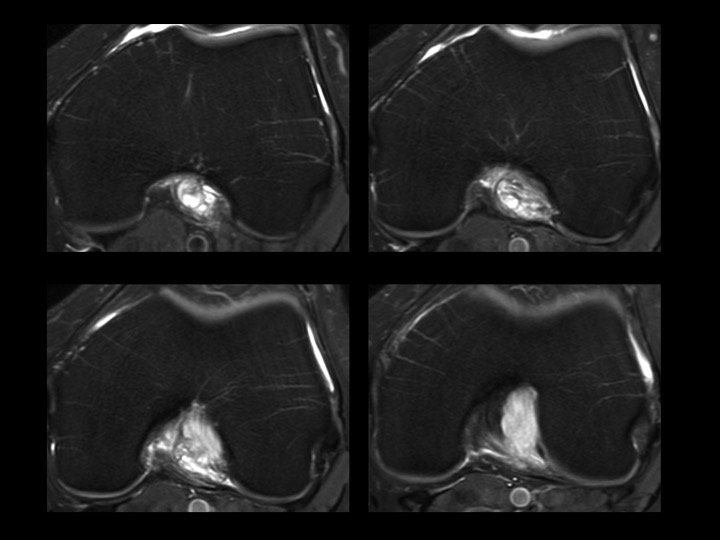

44M worsening knee pain

There is diffuse intrasubstance mucoid degeneration and expansion of the ACL with only small septated ACl ganglion near the femoral origin. This is typically seen in older individuals, but I like to think this gentleman is quite young. No other pathology on MRI. Apparently treatment is varied; Ive only found small series with good outcomes, but no mention of time to clinical follow up. It seems in this case that judicious debridement would be difficult, as the entire ligament seems to be rotten to the core. Reference article.

anterior cruciate ligament ( RID2781 )